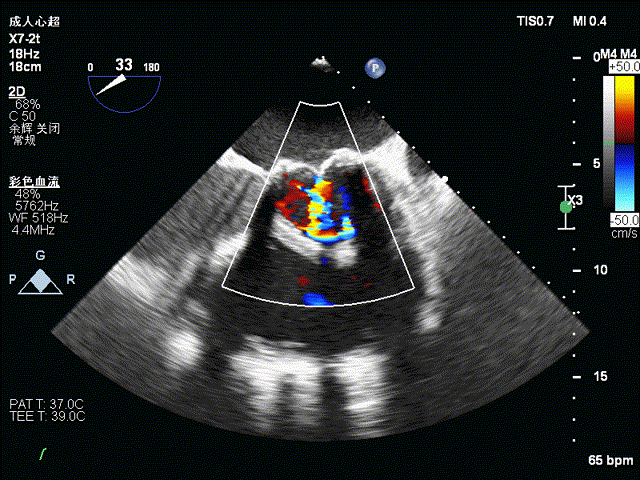

术前食道超声示:

术前食道超声